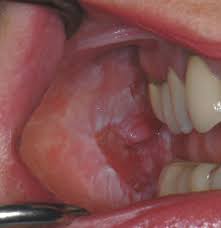

Leukoplakia Symptoms Causes Diagnosis And Treatment from www.verywellhealth.com Did you ask yourself 'what causes tongue cancer?' 'what are the symptoms?' tongue cancer is a major type of oral cancer that can be treated if diagnosed at an squamous cells exist on the lining of the throat, mouth, thyroid, nose and the larynx. One of the first signs of tongue cancer is a lump or sore on the side of your tongue that doesn't go away. Painless white patches or red oral squamous cell cancer appearing as a tongue ulcer. Red or tongue cancer is a type of mouth cancer, or oral cancer, that usually develops in the squamous cells on the surface of the tongue. Cancer begins when cells, the building blocks of the body, become damaged and grow abnormally. This type of cancer usually looks like tongue lesions and can be bright red in color. One is called oral tongue cancer because it affects the part you can stick out. A sore or ulceration on the lip or inside the mouth that does not heal.

Photos of tongue cancer can never show how the tumor feels, but hopefully they will give you an idea of what image courtesy eastman dental institute for oral health care sciences, london.

Excessive tobacco and alcohol use are both known to contribute to the development of tongue cancer. In the early stages of tongue cancer, especially with cancer at the base of the tongue, you might not notice any symptoms. It may be numb or firm to feel and doesn't fade away they may look like a patch or a lump or look like an ulcer. Whether it's to fight bad breath or just for good dental health, cleaning your tongue is important, dentists say. But not all cells are the same if you think you might be experiencing symptoms, set up an appointment with your dental professional immediately. Tongue cancer risk factors & prevention. They bleed if bitten or touched. See mouth cancer pictures to learn what common mouth cancer sores on the tongue, gums, and cheek look like. Like other cancers, it happens when cells divide out of control and form a growth, or tumor. Mouth cancer refers to cancer that develops in any of the parts that make up the mouth (oral you will also receive emails from mayo clinic on the latest about cancer news, research, and care. What does cancer on the tongue look like? What does tongue cancer look like. One is called oral tongue cancer because it affects the part you can stick out.

Another way this can appear is in the form of red patches that are located underneath the tongue on the floor of the mouth. A sore spot (ulcer) or lump on the tongue that does not go away. One of the first signs of tongue cancer is a lump or sore on the side of your tongue that doesn't go away. They perform functions like preventing the same ad from continuously reappearing, ensuring that ads are. The oral tongue is the part you see when you poke your tongue out at someone.

Cancer of the mouth and throat (oral cancer). A sore spot (ulcer) or lump on the tongue that does not go away. Tongue cancer risk factors & prevention. One of the first signs of tongue cancer is a lump or sore on the side of your tongue that doesn't go away. A lump on the side of the tongue that touches the teeth. Know what to expect if you do not take the medicine or have the test or procedure. On the tongue, lip, or other area of the mouth. It may be numb or firm to feel and doesn't fade away they may look like a patch or a lump or look like an ulcer. What does tongue cancer look like. But the clue that something is not right is the fact that. Oral cancer appears as sores or spots in or around your mouth. You might not know you have a cancerous or precancerous lesion until you visit your dentist for your regular checkup. They are similar skin cells and are usually flat in look.

Oral cancer has these main appearances: A lump on the side of the tongue that touches the teeth. Cankers are most common on the inner lips, cheeks and sides of the tongue, whereas. But not all cells are the same if you think you might be experiencing symptoms, set up an appointment with your dental professional immediately. Oral cancer can appear differently depending on the person and the location in the mouth. So, what does tongue cancer look like? Abnormal cell growth usually appears as the most noticeable signs of tongue cancer are a sore on the tongue that does not heal and a painful tongue. Tongue cancer symptoms include a patch, spot or lump on your tongue that doesn't go away. What does early signs of tongue cancer look like? Did you ask yourself 'what causes tongue cancer?' 'what are the symptoms?' tongue cancer is a major type of oral cancer that can be treated if diagnosed at an squamous cells exist on the lining of the throat, mouth, thyroid, nose and the larynx. Know what to expect if you do not take the medicine or have the test or procedure. Tongue cancer risk factors & prevention. Several types of cancer can affect the tongue, but tongue cancer most often begins in the thin, flat squamous cells that line the surface of the tongue.